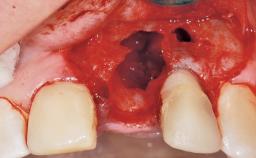

Immediate Flapless Placement of an Implant in a Maxillary Right Lateral Incisor Site

This 43-year-old male patient, a non-smoker, came to our practice because of a fracture of tooth 12 caused by a bicycle accident. Due to the combined para- and infrabony crown and root fracture, tooth extraction, and subsequent implant placement were suggested to the patient as the therapy of choice. The patient had high esthetic expectations with regard to the treatment outcome and asked for an immediate fixed provisional restoration. His individual esthetic risk profile summed up to a medium esthetic risk.

Placement Protocol Immediate implant placement

Tooth Site Maxillary incisor or canine

Socket Morphology Single-root socket

Socket Integrity Sufficient, with intact bone walls

Bone Volume Sufficient, with intact walls